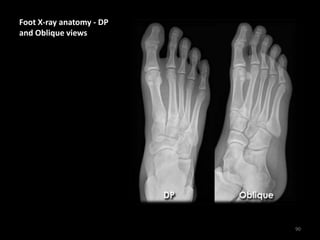

Foot X-ray anatomy - DP

and Oblique views

• Hindfoot = Calcaneus +

Talus

• Midfoot = Navicular +

Cuboid + Cuneiforms

• Forefoot = Metatarsals

+ Phalanges

• 1 = Hind-midfoot

junction

• 2 = Mid-forefoot

junction =

Tarsometatarsal joints

(TMTJs)

Metatarsals and phalanges

of the toes are numbered 1

to 5

1 = Big toe

5 = Little toe

MC = Medial Cuneiform

IC = Intermediate

Cuneiform

LC = Lateral Cuneiform